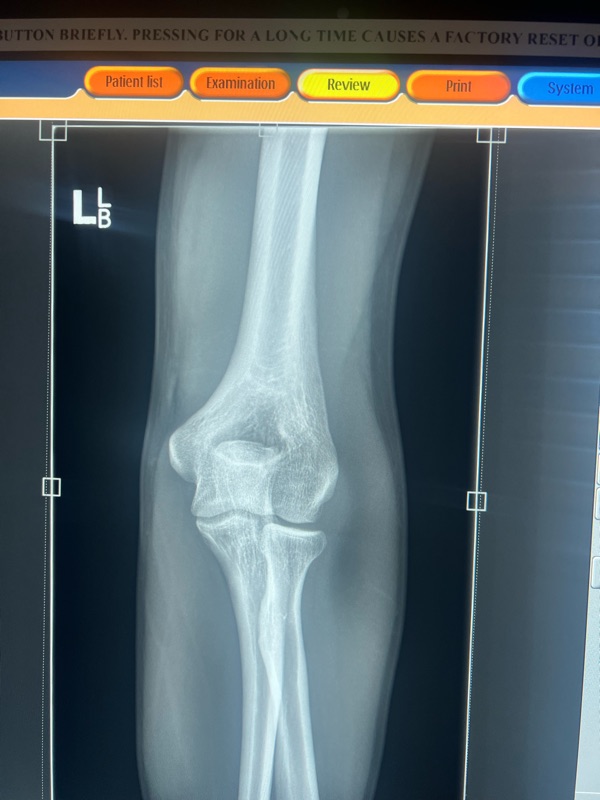

it ended like this! Not amazing but luckily nothing broken. A couple of hours at Mansfield hospital. We left had dinner and met Andrew and Luce at the camp ground and camped the night. Harry was pretty disappointed he didn’t get to race but one’s still a nice weekend away.

Ended like this…